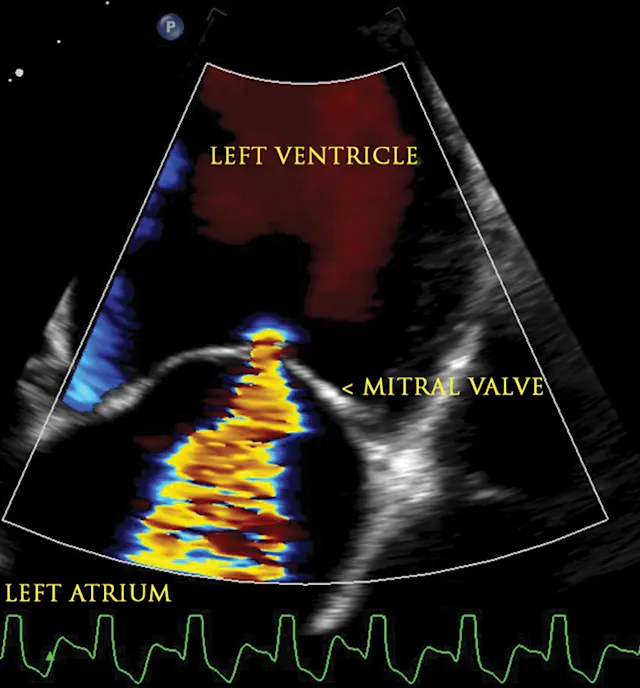

An echocardiogram and thoracic radiographs were obtained. The echocardiogram revealed decreased left ventricular (LV) wall thickness, severe dilation of the LV chamber (ie, eccentric hypertrophy), and severely reduced LV systolic function. Severe left atrial enlargement with a moderate degree of centrally directed left atrioventricular valve regurgitation (suspected functional) was observed. The left atrioventricular valve leaflets appeared normal in thickness with poor coaptation due to annular stretch. In addition, there was mild dilation of the right atrium and ventricle with a mild degree of right atrioventricular valve regurgitation. Results of echocardiography were consistent with dilated cardiomyopathy (DCM; Figures 1-4).2,3

Figure 1

2D echocardiographic image of the left ventricle from the right parasternal short axis view. There is decreased thickness of the LV walls and severe dilation of the LV cavity consistent with DCM.